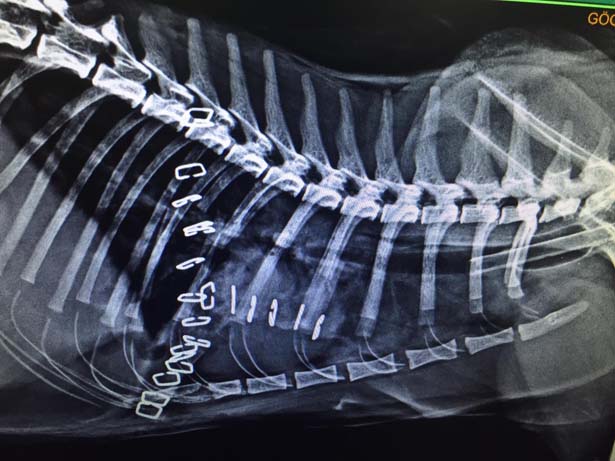

Zonguldak'ta ameliyata alınan kedinin soluk borusundan 1,5 santimlik taş çıkarıldı.

Kastamonu'da hayvanseverlerin baktığı 2 yaşındaki kedi nefes alıp vermekte sorun yaşadı. Ardından hayvanseverler hasta kediyi Kastamonu'da veteriner kliniğine getirdi. Ancak veteriner kliniğinde yeterli ekipman olmadığı için kedi Zonguldak'a nakledildi. Zonguldak Veteriner Kliniğinde röntgeni çekilen kedinin soluk borusunda 1,5 santimlik taş olduğu tespit edildi. Veteriner hekimler Önder Alkan ve Suat Ulucak tarafından 4 saat süren ameliyatla kedinin soluk borusundaki taş çıkarıldı. Yoğun bakıma alınan kedinin durumunun iyi olduğu öğrenildi.

Veteriner Hekim Önder Alkan, ''Dün akşam Kastamonu ilinden geldi bize hastamız. Yaptığımız tetkiklerde soluk borusunda yabancı cisim tespit ettik akciğerin giriş bölgesindeydi kalbin üzerinde kötü bir solunumu vardı boğulmak üzereydi. Açık bir ameliyat geçirdi. Soluk borusundan bir taş çıktı. Zorlu bir ameliyattı 6 saat sürdü. Ameliyattan sonra solunumu düzeldi. Akciğerler düzeldi 3 günlük sıkıntılı bir durumu var. Oynarken muhtemelen oldu aşağıya kadar indi. Bir anda solunum güçlüğünden dolayı anlamış vatandaş ve hemen veterinere getiriyor ve yapılan tetkiklerde yabancı cisim görülüyor. Bu ameliyat için otomatik solumun sistemi gerekiyor. Bu sistem olan yerlerde bu ameliyatlar yapılıyor. Zor ve riskli bir ameliyat” şeklinde konuştu.